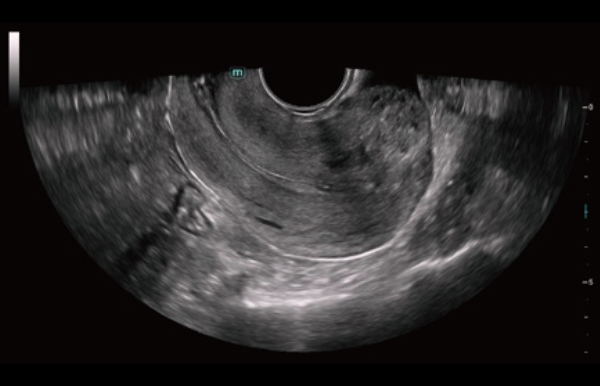

The Consona features new and concrete solutions, that efficiently help you to carry out smooth diagnoses for extensive type of patients.

No matter your routine is in hospitals, clinics, or you are honing skills in General Imaging applications, women's health care or cardiovascular specialties, you will find highly powerful tools available on this series to keep you stay ahead.

Comprehensive Imaging Solutions Powered by ZST+

The ZST+ platform is an extraordinary innovation, representing an ultrasound evolution. Transforming ultrasound metrics from conventional beam-forming to channel data based processing. It overcomes the traditional trade-off limitation among spatial resolution, temporal resolution and tissue uniformity, delivering exceptional image quality for infinite imaging solutions with non-stop improvements.